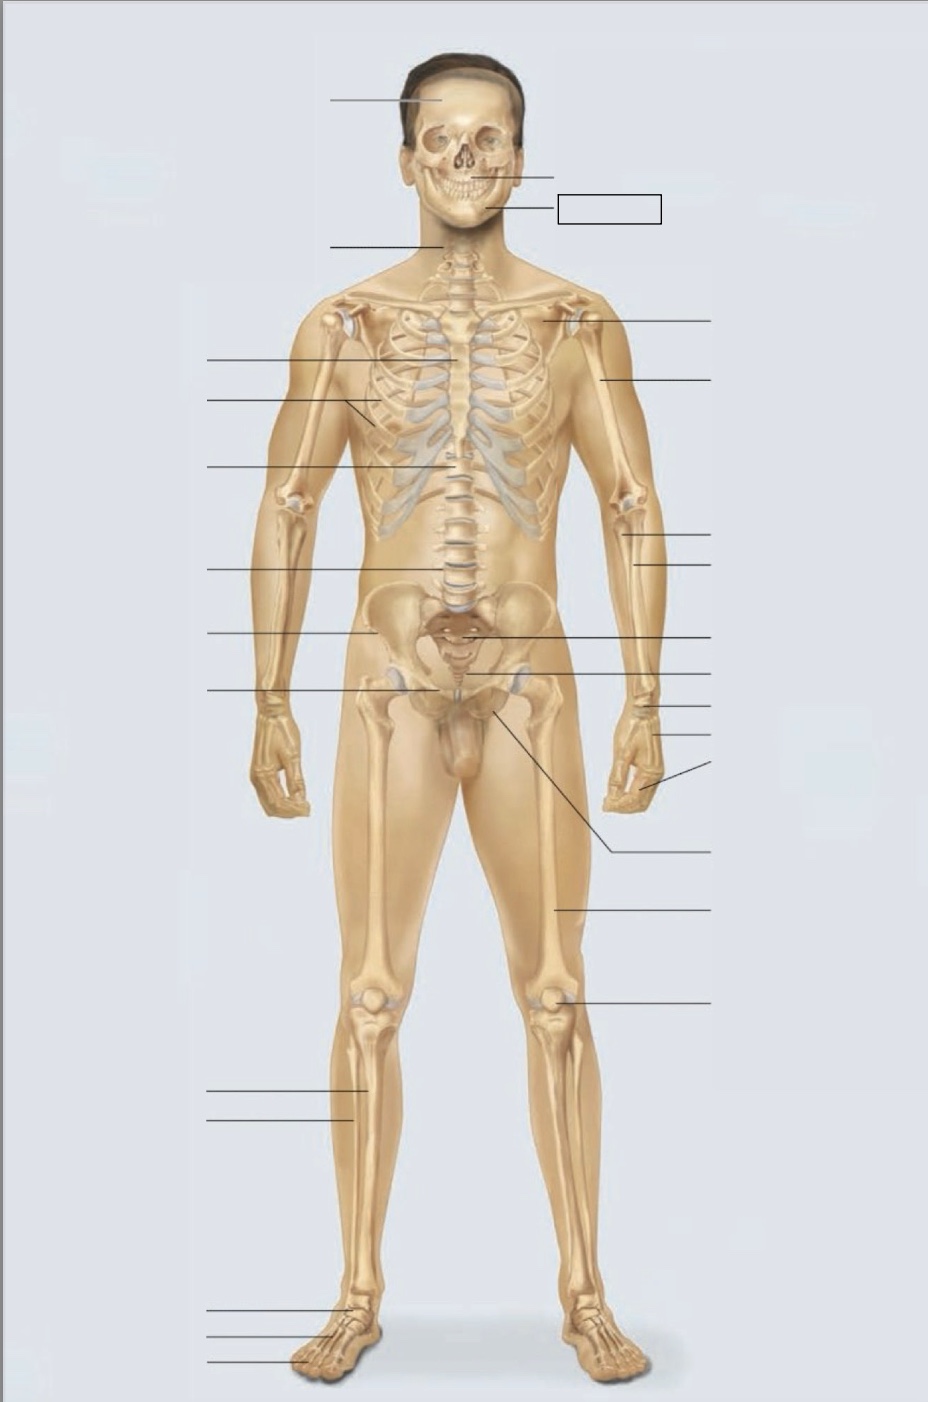

maxilla

mandible

scapula

humerus

ulna

radius

sacrum

coccyx

carpals

metacarpals

phalanges

ischium

femur

patella

phalanges

metatarsals

tarsals

fibula

tibia

pubis

ilium

lumbar vertebrae (L4)

thoracic vertebrae (T11)

ribs

sternum

cervical vertebrae

skull